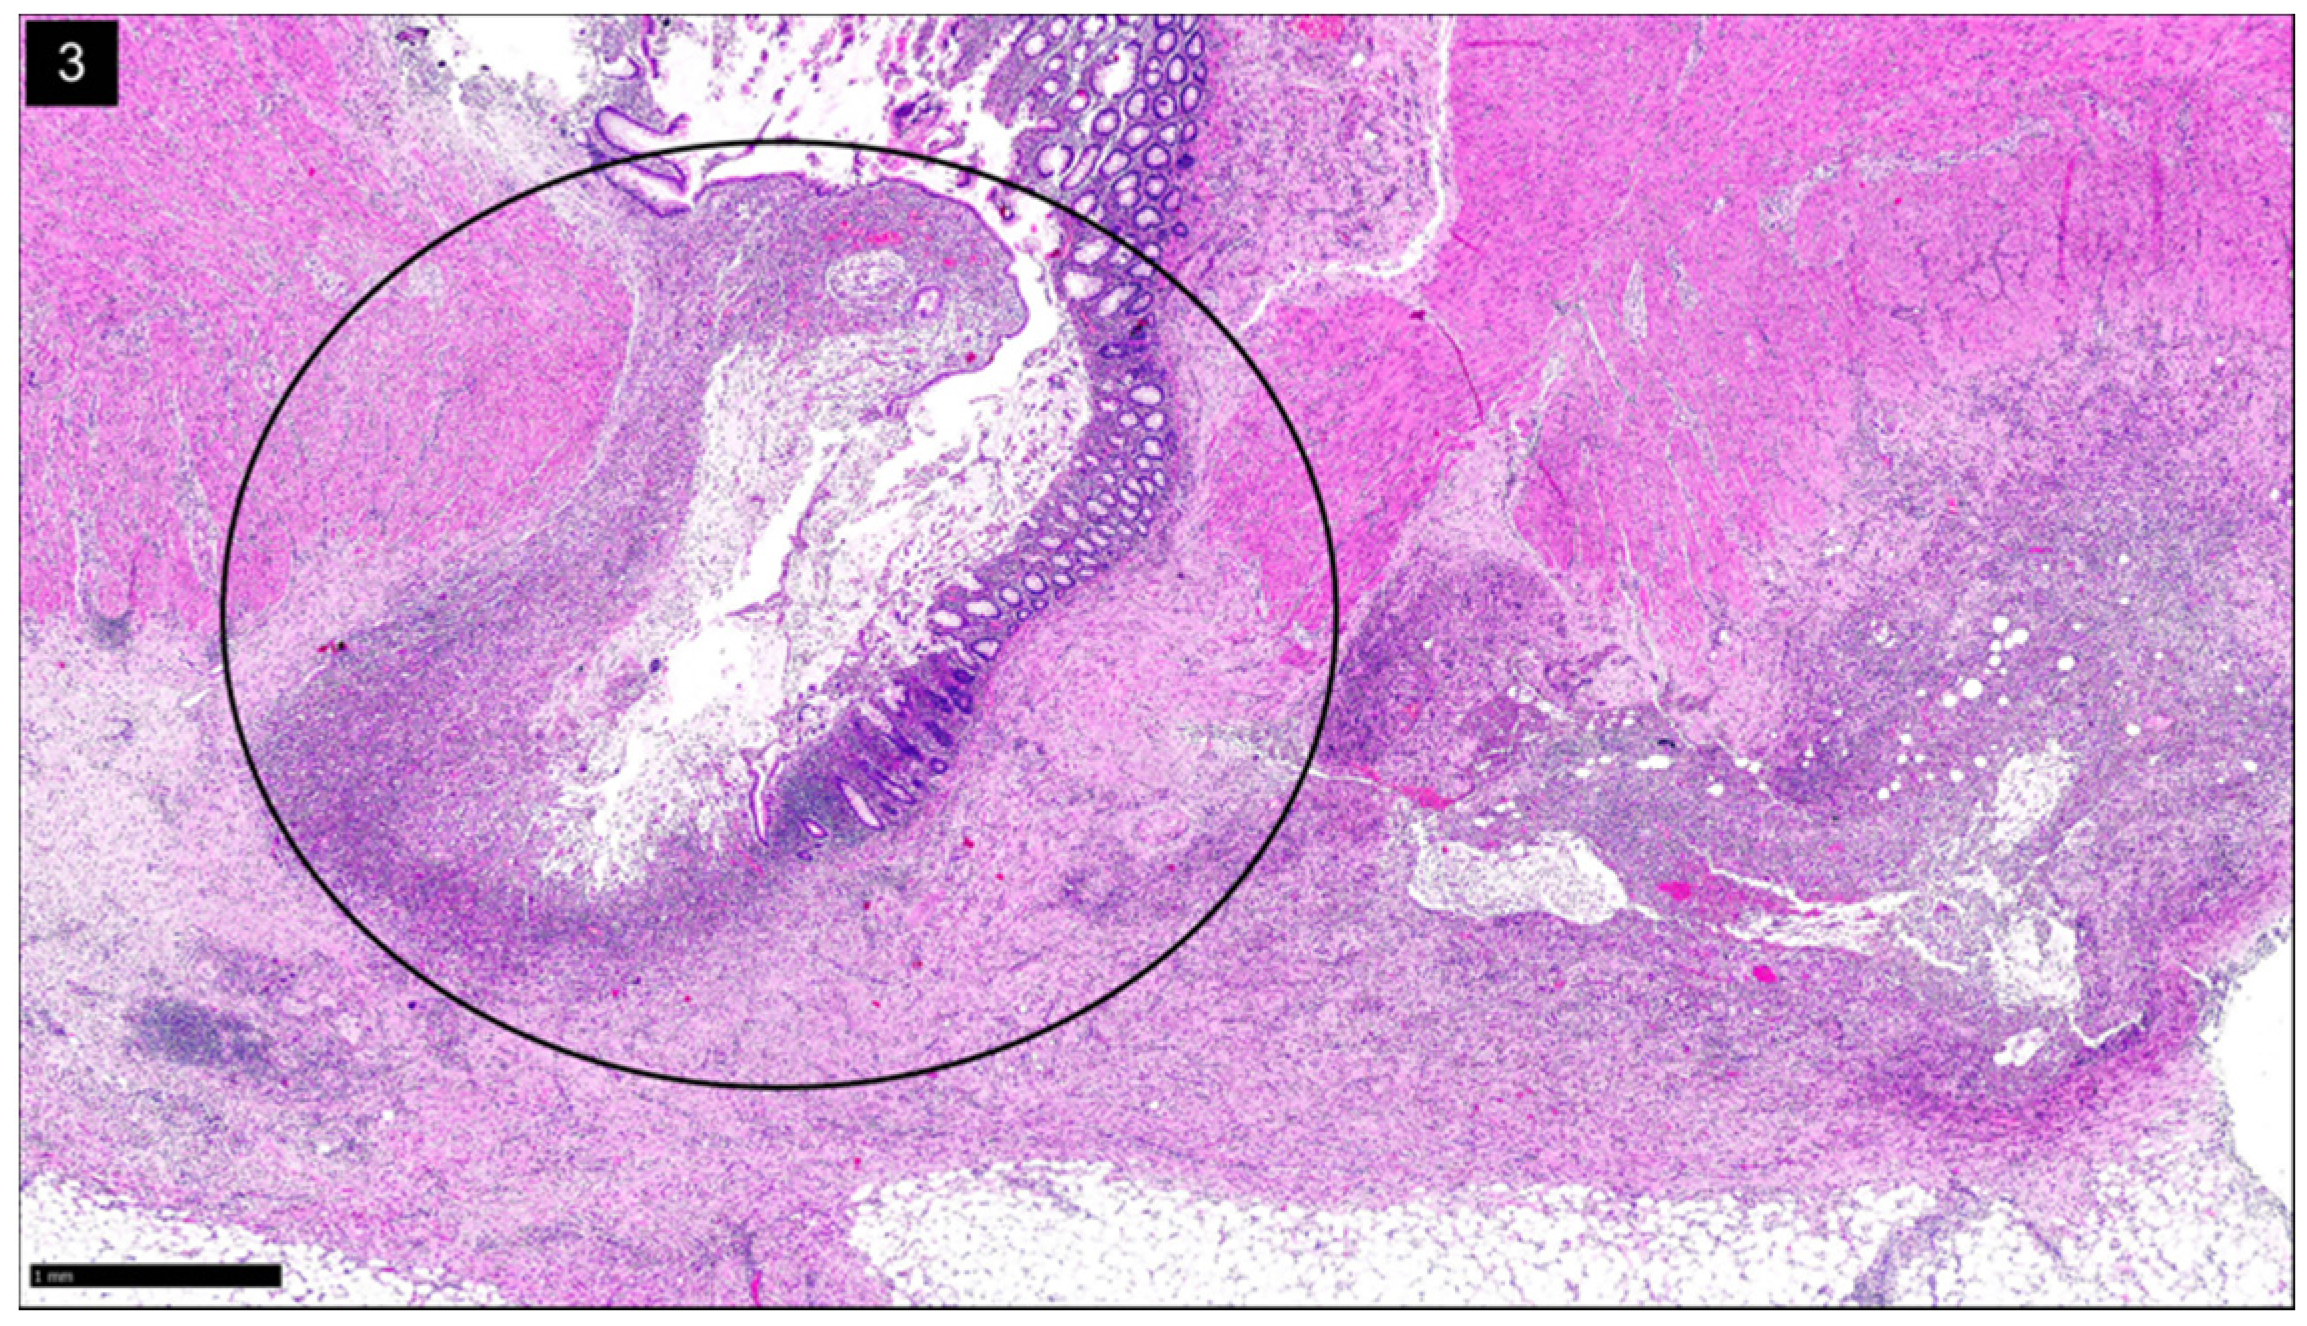

Figure 2.

Diverticular Disease Associated Colitis, a.k.a. Segmental Colitis Associated with Diverticulosis (SCAD): H&E stain shows chronic active colitis (inset) in a segment of sigmoid colon with diverticular disease (Circle) (H&E, ×15).

SCAD is characterized by nonspecific segmental inflammation in the sigmoid colon surrounded by multiple diverticula [4,11,12,25]. The initial presentation is often rectal bleeding and in some, diarrhea or abdominal pain [12]. SCAD is typically benign and self-limited [4]. SCAD differs from diverticulitis because the individual diverticula are not involved; histologically, this shows inflammation within the interdiverticular mucosa rather than the diverticular orifices [4,12]. Additionally, a chronic active colitis pattern of injury with crypt distortion and cryptitis is seen on histology (Figure 2). Its prevalence varies between 1.15% and 11.4% among those diagnosed with diverticular disease [11].